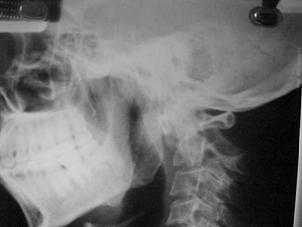

TRAUMA CERVICALA

Incidenta laterala Incidenta

laterala Incidenta

Aspect normal Imagine

incompleta Aspect

normal